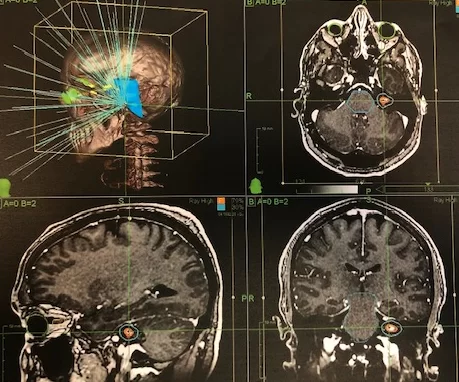

Ενδοκαναλικό Ακουστικό Νευρίνωμα αριστερά

Ασθενής άνδρας, 39 ετών ο οποίος παρουσίασε έκπτωση ακοής αριστερά, διαγνώστηκε με μικρή ενδοκαναλική (δηλ. εντός του έσω ακουστικού πόρου) εξεργασία σύστοιχα, συμβατή με μικρό